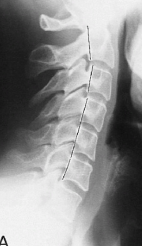

Q what is the name of this measurement? and what is the average + range?

A: George's Line

assesses the posterior surfaces of the vertebral bodies for a smooth vertical alignment. No average or range is specified.